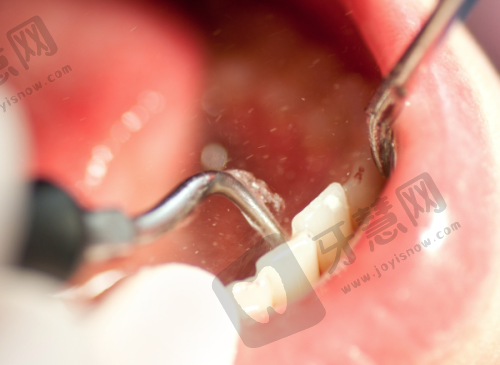

6. 全瓷牙冠美容修复:选用德国威兰德、美国3M等品牌瓷冠,生物相容性好,色泽自然,边缘密合度达99%,可使用10年以上。

6. 广东东莞石碣专致口腔德国威兰德全瓷冠:3500 - 4500元/颗

12. 广东东莞石碣专致口腔烤瓷牙冠:1500 - 2500元/颗(镍铬合金内冠)